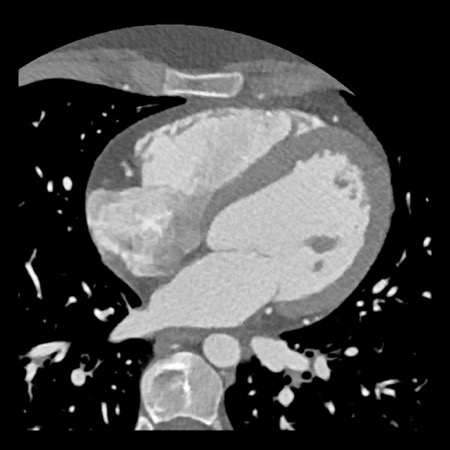

case 5 – CTA overestimates stenosis due to calcium

First, scroll through the CTA images.

How would you describe the findings on the coronary CTA?

Continue with the curved MPR images of the same patient.

The findings are:

- Long, partially

calcified plaque in the LM-LAD causing moderate stenosis (50-69%) (white

arrows).

This segment of the LAD is difficult to evaluate because of blooming and step

artefacts. - Calcified plaque in

the D1 causing severe stenosis (70-99%) at the origin (white arrows). - Partially calcified

plaque proximal from the LCX stent with moderate (50-69%) stenosis (white

arrow).

LCX stent patent, no stenosis (black arrows). - Calcified plaques

in the proximal RCA with minimal stenosis (<25%) (white arrows).

RCA stent patent (black arrows).

Non-calcified plaque distal to the stent causing minimal stenosis (white

arrowheads).

Another non-calcified plaque in the distal RCA causing minimal stenosis

(<25%) (white arrows).

Partially calcified plaque in the distal RCA with mild stenosis (25-49%) (two

white half-arrows). - Total plaque burden

is extensive (P4).

Due to severe stenosis in D1, extensive plaque burden, some

non-diagnostic segments and a stent this patient classifies as CAD-RADS

4A/P4/N/S, which means that this patient needs further workup.